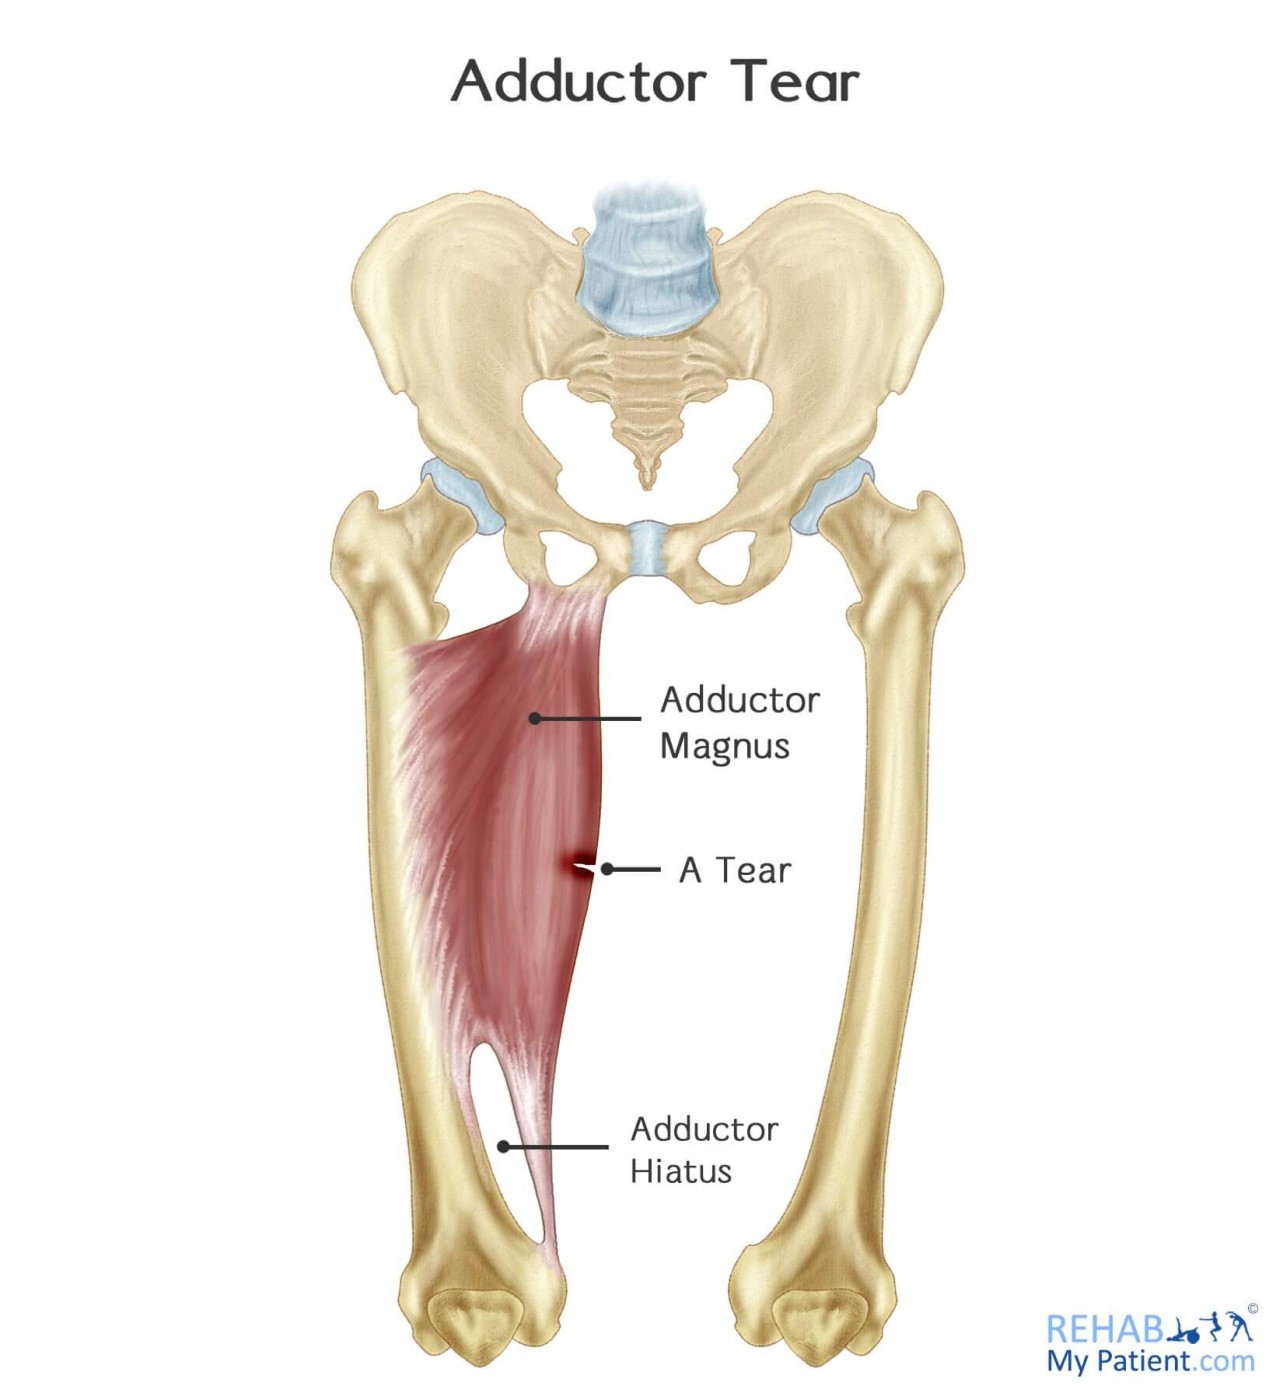

From www.rehabmypatient.com

Adductor Tear Rehab My Patient Hip Abductor Tear learn about the causes, symptoms, diagnosis and treatment of hip abductor tendon tears, a common injury in runners and athletes. lastly, women more commonly demonstrate symptomatic tears compared to men (tibor 2008). hip abductor tears are common in runners and athletes who overuse or injure the buttock muscles. hip abductor or gluteal tendon tears are a. Hip Abductor Tear.

Adductor Muscle

Adductor Muscle Hip Abductor Tear hip abductor muscle atrophy, defined as 25% gross muscle wasting seen on mri, was found more frequently in hips with tears of the distal abductor tendons than in hips in the control group, but no statistically significant association was found. Many of these tears often go. learn about the causes, symptoms, diagnosis and treatment of hip abductor tendon. Hip Abductor Tear.